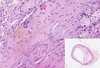

Atherosclerosis of the Artery

Adventitia

Atheroma

Clefts after washing up Cholesterol Crystals

Granular Deposits of Calcium

Intima

Lipophages

Lumen and Fibrous Cap

Lymphocytes

Media

Necrotic Detritus

New Blood Vessels